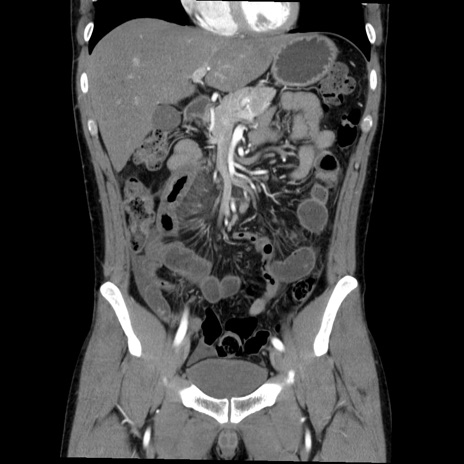

症例36(冠状断像)

【症例】20歳代 男性

【主訴】心窩部痛

【現病歴】今朝より上腹部痛あり。一旦軽快していたが再度出現したため救急要請。昨日夕に白身の魚を含む刺身を食べた。

【身体所見】BP 136/89mmHg、HR 74/min、BT 37.0℃、腹部:膨満、軟、心窩部に圧痛あり。反跳痛なし、筋性防御なし、腸雑音やや亢進あり。

【データ】WBC 17700、CRP 0.48

横断像